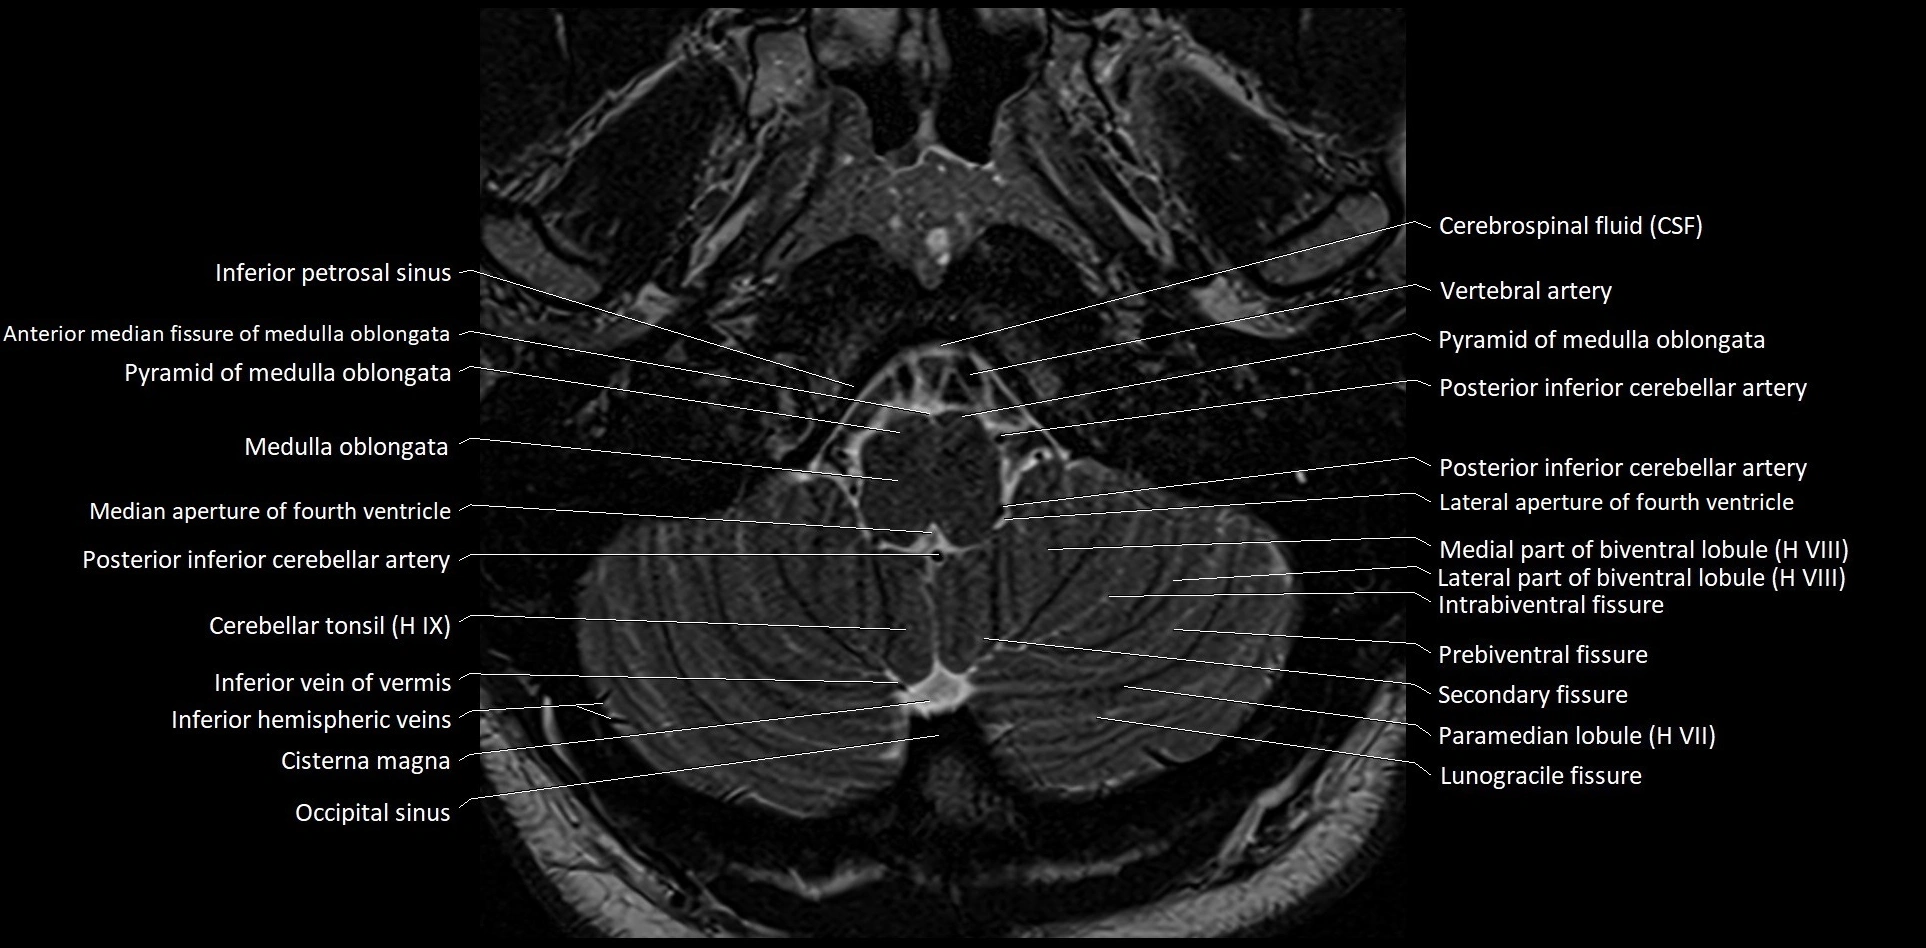

MRI images